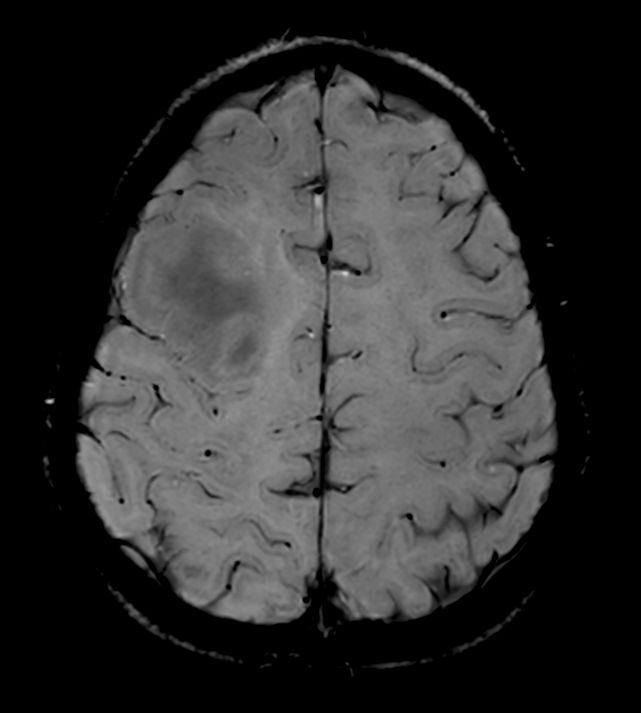

Diffusion (ADC)